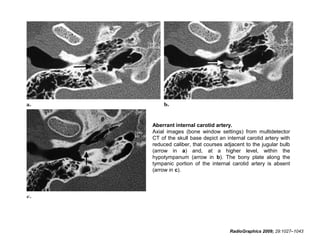

• On axial CT images, the presence of an aberrant

intratympanic internal carotid artery may be signaled by:

(a) an internal carotid artery with a reduced diameter

and a course posterior and parallel to the jugular bulb

(b) a mass in the hypotympanum

(c) deficiency of the bony plate along the tympanic

portion of the internal carotid artery

(d) absence of the vertical segment of the carotid canal.

• On coronal CT images, the important features are a

hypotympanic mass and enlargement of the inferior

tympanic canaliculus.

Aberrant internal carotid artery.

Axial images (bone window settings) from multidetector

CT of the skull base depict an internal carotid artery with

reduced caliber, that courses adjacent to the jugular bulb

(arrow in a) and, at a higher level, within the

hypotympanum (arrow in b). The bony plate along the

tympanic portion of the internal carotid artery is absent

(arrow in c).

RadioGraphics 2009; 29:1027–1043